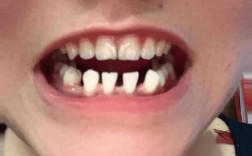

• 牙齿矫正只矫正上面?上下咬合问题这样能解决吗?

牙齿矫正只矫正上面?上下咬合问题这样能解决吗?

牙齿矫正是否可以只针对上牙进行,是很多存在牙齿问题者常有的疑问,正畸治疗并非必须上下颌同时进行,是否存在“只矫正上牙”的可行性,需结合牙齿问题的具体类型、咬合关系、颌骨发育情况等多维度因素综合判断,本文将围绕“牙齿矫正只矫正上面”的适用情况...